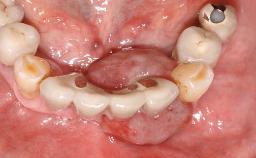

Removal of a Malpositioned Implant and Direct New Implant Placement with Simultaneous Contour Augmentation using GBR

A 35-year old female patient was referred to the Department of Oral Surgery and Stomatology at the University of Bern, Switzerland, for examination of an implant site that had exhibited clinical signs of slightly delayed wound healing. In addition, the referring clinician found no evidence for a facial bone wall when she raised a flap to gain access to the implant for abutment connection. Four months earlier, she had inserted a bone-level implant in a single-tooth gap, where the lateral incisor had been extracted due to a chronic periapical lesion on the mesial aspect of the root. Implant placement was combined with simultaneous bone augmentation using deproteinized bovine bone mineral (DBBM, Bio-Oss®; Geistlich, Wolhusen, Switzerland) and a collagen membrane (Bio- Gide®; Geistlich), followed by primary wound closure. The patient also provided the postsurgical radiograph that displayed the implant with a 3.5-mm healing cap.

Case Type Single-Tooth Space

Jaw Maxilla

Area Anterior

# of Teeth 1

# of Implants 1